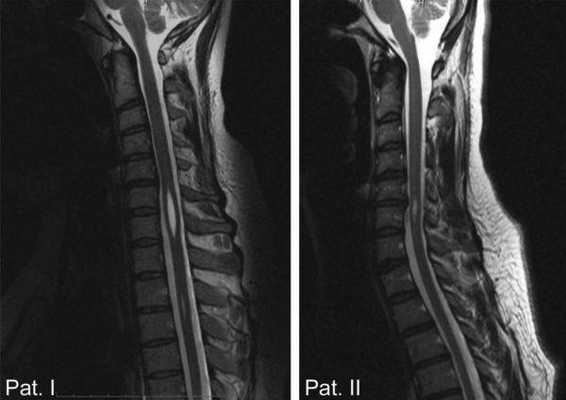

Рентгенологические методы диагностики могут выявить трофические проявления сирингомиелии в виде остеопороза, разрушения костных элементов сустава и т. п. Точно диагностировать сирингомиелию позволяет МРТ позвоночника, а при невозможности ее проведения - миелография. Эти методы обследования дают возможность увидеть сирингомиелические полости в спинном мозге и стволе.

- МРТ;

На заметку! Самым информативным и достоверным методом диагностики сирингомиелии является магнитно-резонансная томография.